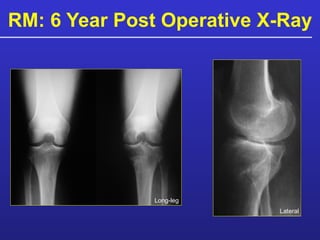

Patient Example: RM 57 Male Long-leg MRI Injury: Football tackle 1978  Previous Meniscectomy: 1978, 1993 Moderate varus mal alignment ( ≤ 7°) MFC OCD lesion

RM: 6 Year Post Operative X-Ray Long-leg Lateral